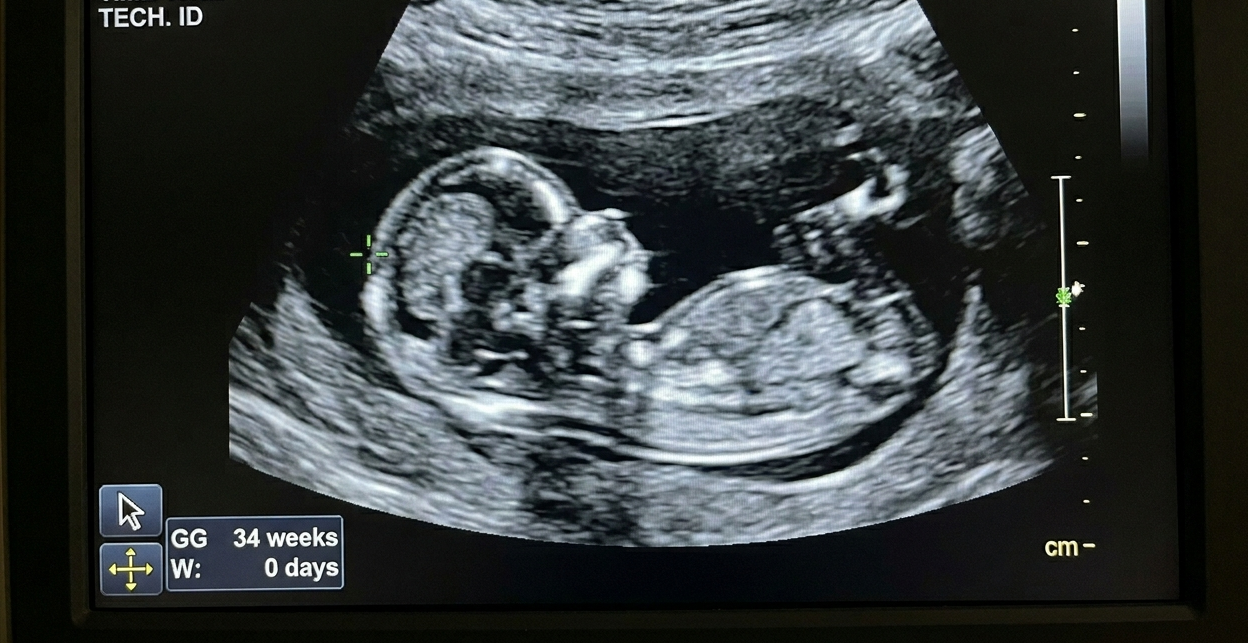

Are you pregnant and experiencing swelling of your hands, feet, or face? These are signs that your body is not metabolizing water properly. This can happen for two reasons in Chinese Medicine - a weakness in the Kidneys or a sign that your energy has become stagnant. Both can easily occur during pregnancy, and here's why:

Feeling irritated? sighing a lot? As the mother progresses into her third trimester of pregnancy, the baby gains weight rapidly at about 1/2 a lbs per week. The increased weight not only makes you feel heavier, but can leave you feeling stagnant as well. If you experience swelling in your hands, and face these signs indicate that your energy has become stagnant according to Chinese Medicine. You may even feel some achiness in your finger joints. If so, it may be time to include some stretching, or prenatal yoga in your morning rituals to promote the flow of your energy and alleviate stagnation. Foods that can help are leafy greens, peppermint tea, and spices such as garlic, onions, or chives in moderation.